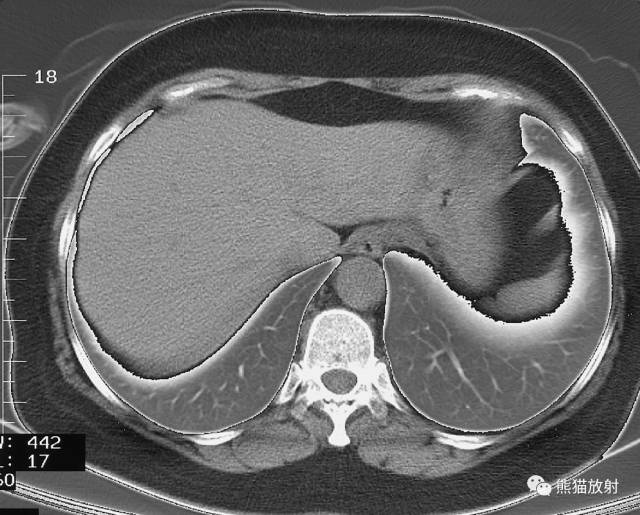

轴位断层肺段分布

上叶【S1:尖段、 S2:后段、 S3:前段】

中叶【S4:外段 、S5:内段】

下叶 【S6:背段、S7:内基底段、S8:前基底段、S9:外基底段、S10:后基底段】

左肺

上叶【S1+2:尖后段、S3:前段、S4:舌叶上段、S5:舌叶下段】

下叶【S6:背段、S7+8:前内基底段、S9:外基底段、S10:后基底段】